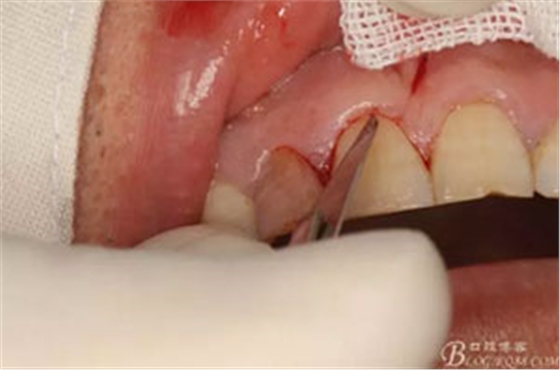

圖7. 角形切口中的齦溝內(nèi)切口情況:11號刀片伸進(jìn)齦溝內(nèi)斜切。

圖8.從垂直切口和水平切口的連接處翻瓣。發(fā)現(xiàn)11和12之間的骨壁有缺損。